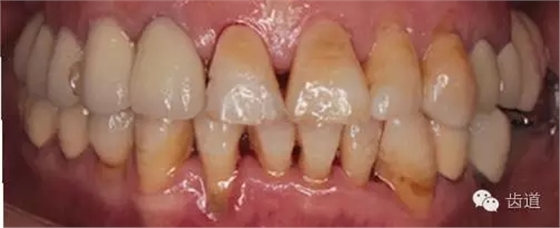

1、全口正面觀

1、治療前

2、治療后